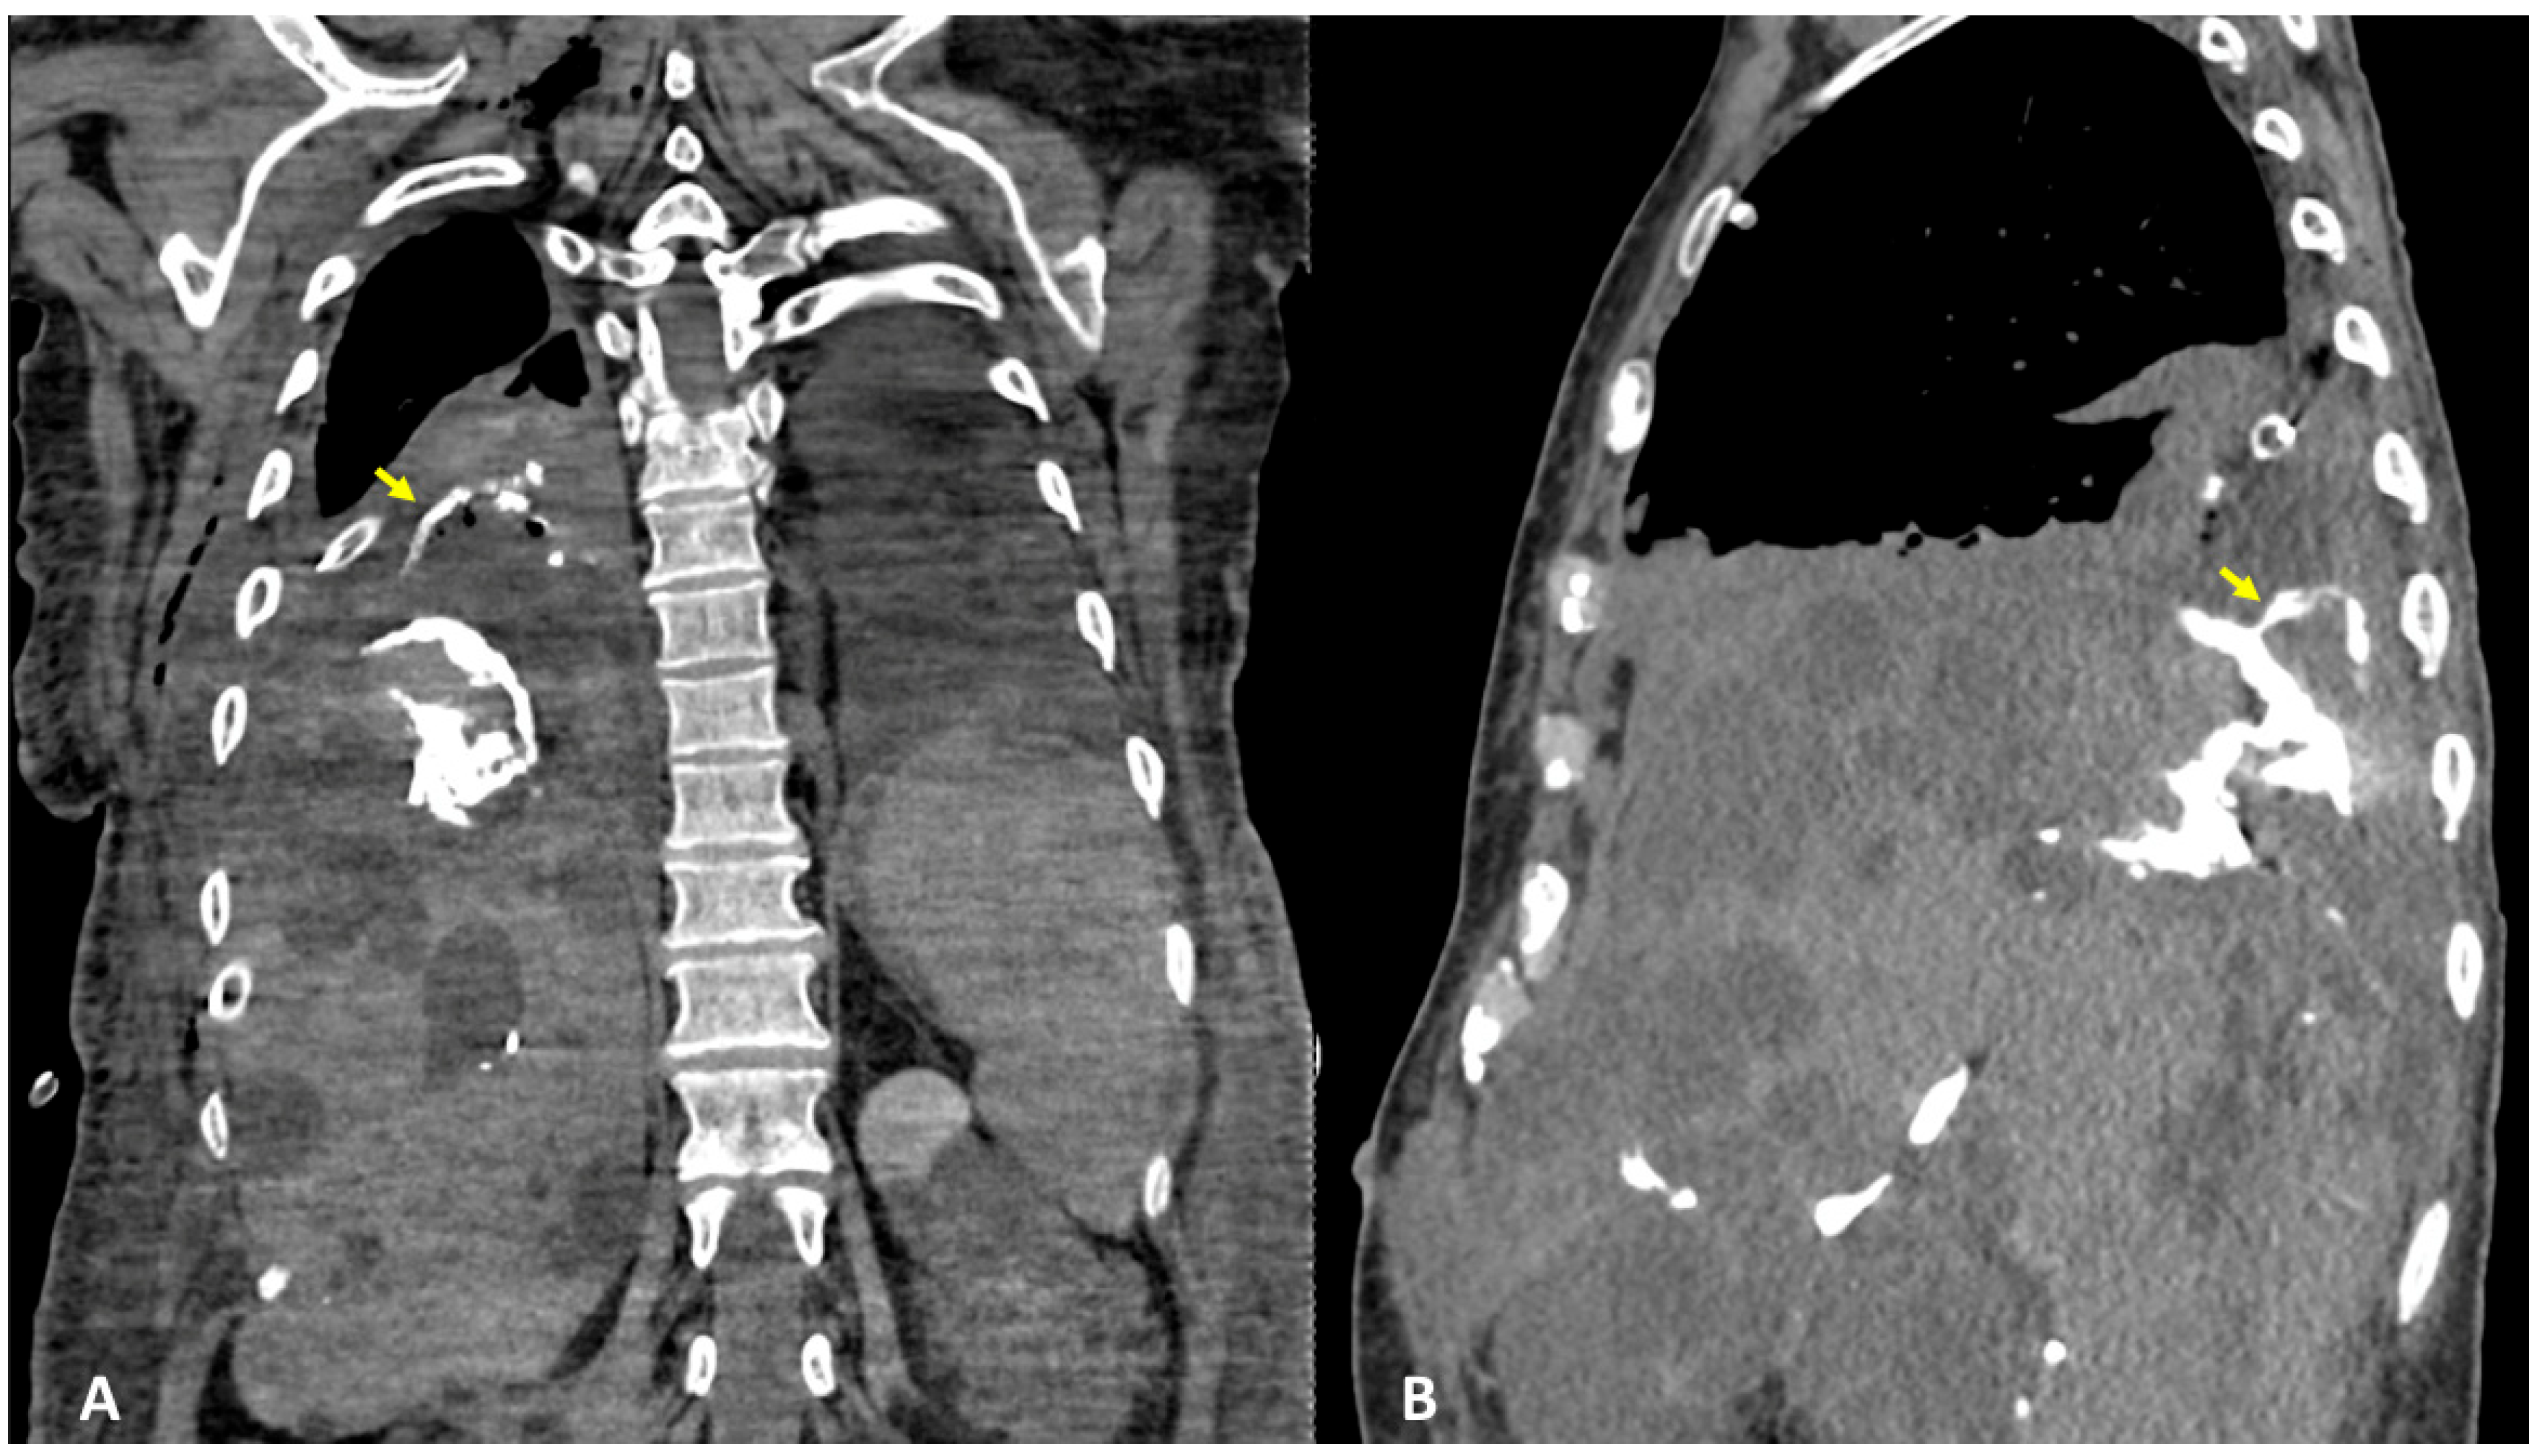

3.1. Case #1: Hepato-Thoracic Fistula

3.2. Case #2: Hepato-Thoracic Fistula

3.3. Case #3: Hepato-Thoracic Fistula

3.4. Case #4: Pancreaticopleural Fistula